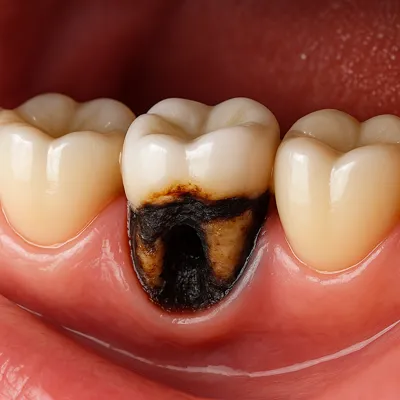

درد دندان بعد از خوردن شیرینی معمولاً نشاندهندهٔ وجود پوسیدگی در سطح عاج دندان است؛ در این مرحله هنوز پوسیدگی به عصب نرسیده، اما قند موجود در مواد غذایی باعث تحریک بافتهای حساس زیر مینا میشود.

احساس درد تیز، تیرکشیدن کوتاه یا سوزش خفیف پس از خوردن شیرینی، چای یا نوشیدنیهای قندی، از نشانههای اولیهٔ این وضعیت است.

در چنین شرایطی، مینای دندان دچار فرسایش شده و راه نفوذ قند و اسید به لایهٔ زیرین (دنتین) باز میشود.

پوسیدگی دندان همراه با گیر کردن خوراکی شیرین بین شیار دندان و التهاب لثه

نمای نزدیک از پوسیدگی شدید دندان و ریشههای عصبی ملتهب در دهان انسان